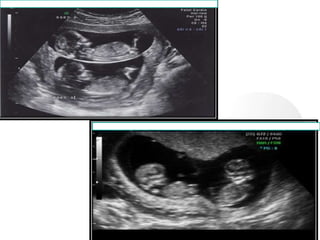

 Multiple Pregnancy- identification of

two gestational sacs indicates twin birth

in 52-63% of cases